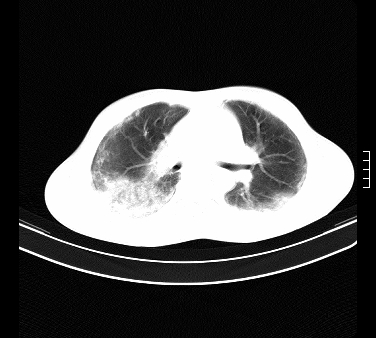

患者,男,17岁,系我院急诊科收治的一例百草枯中毒患者,做ct检查时,距离服药的时间为3天。上传与大家分享

补充:百草枯进入人体内主要分部于肺和骨骼,肺部损伤24小时内出现水肿,2-3天内出现急性呼吸窘迫综合征,1-2周内出现肺纤维化。(引自陈灏珠,实用内科学12版)